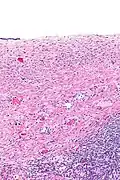

Ovarian serous cystadenoma. The cystic space is at the top of the image. Ovarian parenchyma is seen at the bottom right. H&E stain.

Serous cystadenomas are diagnosed by histomorphologic examination, by pathologists. Grossly, they are, usually, small unilocular cysts that contain clear, straw-coloured fluid. However, they may sometimes be multilocular. Microscopically, the cyst lining consists of a simple epithelium, whose cells may be either:[4]

• be columnar and tall and contain cilia, resembling normal tubal epithelium

• be cuboidal and have no cilia, resembling ovarian surface epithelium